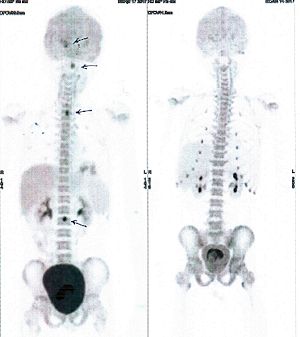

CASE NO: 16 (GLIOMA)

Teenage boy with glioma spreading to the spinal cords (arrows) and urinary retention. After a few treatment, all the cancer went into remission, and there is no more urinary retention.